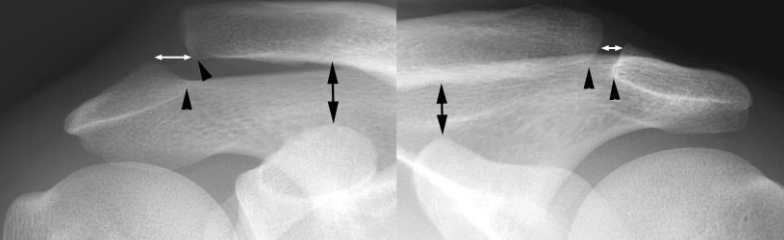

Articulation AC Normal

- Articulation Acromio-claviculaire : <5-8mm

- Distance coraco-claviculaire: <10-13mm

Classification de Rockwood

Grade II

- Déchirure complète du LIG AC

- Pas de déchirure du Lig Coraco-clav

Lig AC sup et inf dechirés, Lig Trapezoide partiellement dechiré

Grade III

- Déchirure du Lig Coraco-clav

- Distance CC <25mm

Lig AC sup et inf dechirés, Lig CoracoClav dechiré